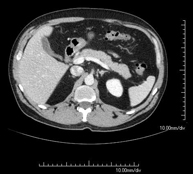

Prova diagnòstica que consisteix en l'estudi de l'abdomen d'alta definició anatòmica (fetge, vesícula biliar, via biliar, pàncrees, melsa, estómac, intestins, ronyons, estructures vasculars, bufeta, úter i ovaris, etc.) mitjançant l'ús d'un equip de TC (Tomografia Computeritzada). Aquestes imatges s'estudien posteriorment en una estació de treball que permet obtenir reconstruccions bidimensionals en diferents plànols de l'espai i també reconstruccions 3D (volumètriques). La majoria d'estudis requereixen l'ús de contrast iodat per millorar la definició de les imatges. - TC Pelvis

Prova diagnòstica que consisteix en obtenir imatges bi i tridimensionals de l'abdomen d'alta definició anatòmica (estructures òssies, estructures vasculars, fetge, pàncrees, vesícula biliar, ronyons, glàndules suprarenals, melsa, intestí prim i gros, bufeta, úter i ovaris, pròstata i vesícules seminals, urèters, etc.) mitjançant l'ús d'un equip de TC (Tomografia Computeritzada). La majoria d'estudis requereixen l'ús de contrast iodat. - TC Fetge

Prova diagnòstica que consisteix en obtenir imatges bi i tridimensionals del ronyó i del sistema urinari d'alta definició anatòmica mitjançant l'ús d'un equip de TC (Tomografia Computeritzada). Es realitza l'estudi abans i després de l'ús de contrast iodat en diferents "fases renals" per a una valoració funcional i anatòmica: parènquima renal, urèters, bufeta urinària, artèries i venes renals, etc. així com les estructures adjacents (vena cava inferior, aorta abdominal, fetge, melsa, etc.). Està especialment indicat quan hi ha sospita de lesions renals, en pacients amb sang a l'orina o hematúria, etc. - TC Urològic